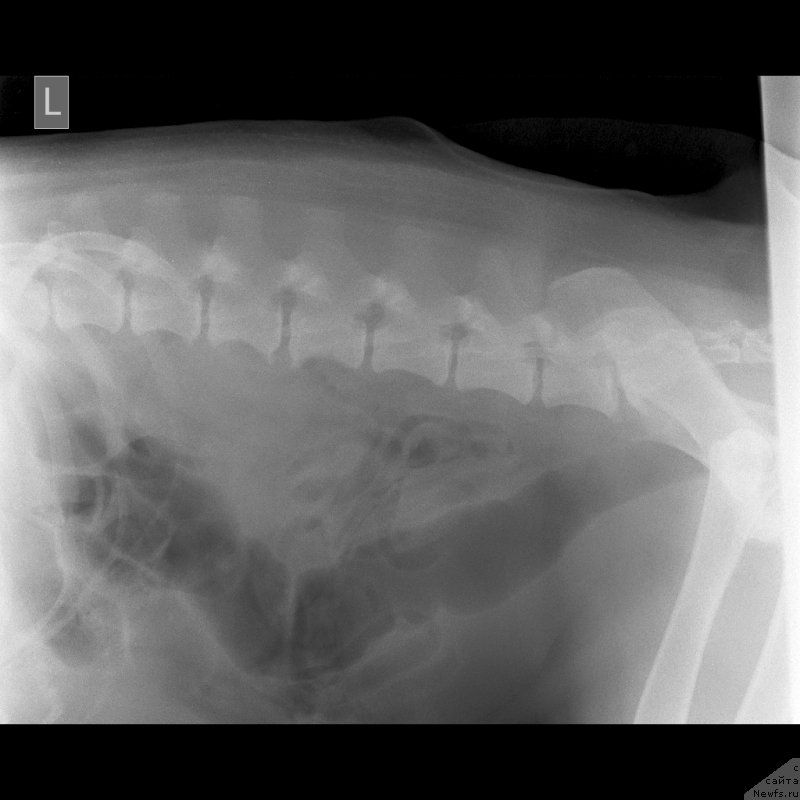

Сделали еще дополнительные снимки.Пес рыдает нон стоп.

Превью фото № 245745

Превью фото № 245746

Превью фото № 245747

По клинической картине и по снимкам - спондилёз поясничного отдела позвоночника. Лечение: первые сутки дексаметазон 4 мг 3 раза /день или преднизолон, можно внутримышечно, и римадил 100мг 3 раза в день.